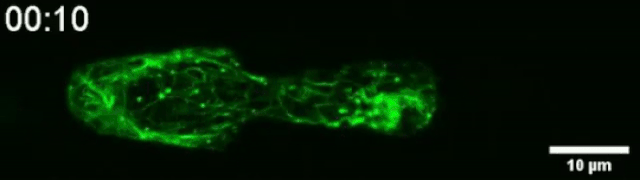

下面这段视频捕捉到了角蛋白在挤压过程中如何聚集在细胞核末端的过程。角蛋白是构成细胞骨架的三种纤维网络之一的组成部分。它在快速构建和拆卸细胞骨架方面发挥着重要作用。

研究人员认为,角蛋白的重排列可能是导致细胞变形的原因。因此,他们用突变的口腔鳞状上皮细胞进行了测试。

突变产生的角蛋白变形与这种组织类型中发现的癌症有关。突变细胞无法突破瓶颈,这表明角蛋白对挤压过程至关重要。当循环肿瘤细胞在体内通过血流传输,可能会被困在毛细血管的瓶颈中。它们可以在同一个地方停留一段时间,这种机械性的限制会导致它们重塑,并通过外渗进入到邻近组织。